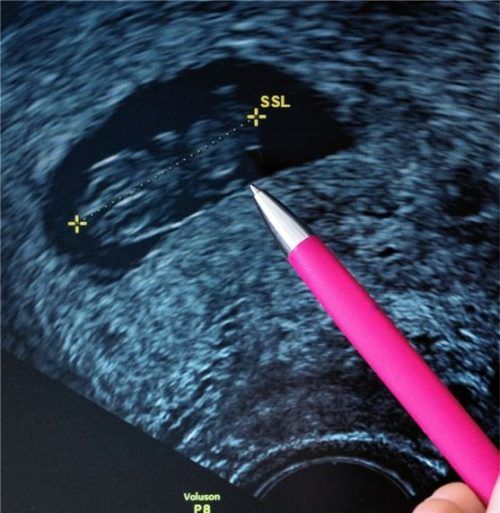

Eine Frauenärztin deutet auf den Kopf eines Fötus im Ultraschall, dessen Scheitel-Steiß-Länge (SSL) von 24,2 Millimetern auf eine Schwangerschaftsdauer von etwa 9 Wochen hinweist.Foto DPA